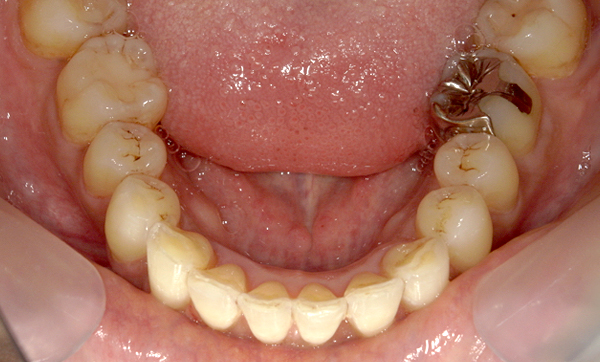

症例:上下顎の部分矯正

症例_009 前歯「八の字/V字型」症例

治療期間:11ヶ月金額:60万円+税40代女性八の字/V字型前歯のガタガタ捻転歯